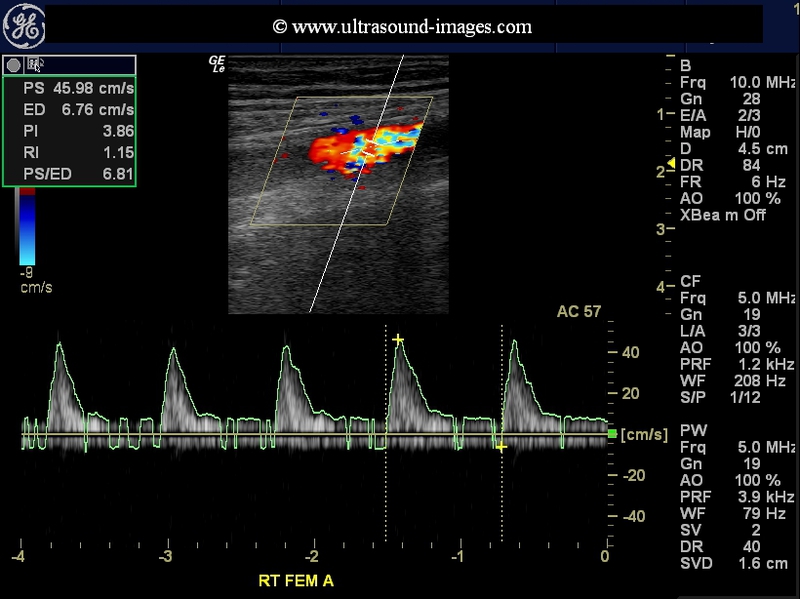

This elderly lady with a history of diabetes has evidence of ischemic changes of the right leg, with onset of gangrene of the toes. Colour Doppler study of the lower limb shows a severe stenosis of the right femoral artery, in its upper third. The diameter of the stenotic segment measured only 1.8 mm.

The prestenotic segment (Rt SFA/ femoral A) shows typical changes- steep upward slope of systole and shouldering of downward slope of systole (see green arrows in femoral A image).

Colour Doppler and spectral Doppler ultrasound examination of the stenotic segment of the right femoral artery shows a peak systolic velocity more than 190 cm/s (Vs). The peak systolic velocity in the pre-stenotic segment was 97 cm/s (Vp). The ratio Vs/Vp is greater than 2 suggesting a moderate to severe stenosis of the affected segment of the femoral artery.

The arterial tree below the femoral including the right popliteal, the right peroneal, posterior tibial and anterior tibial arteries all show moderate dampening off the blood flow in these arteries.

This diabetic male patient shows evidence of darkening of the right toes (see snap above), s/o ischemic changes and onset of pre-gangrene.

Doppler and spectral Doppler waveforms show a severe stenosis of the right SFA with Vs/ Vp ratio in this case = 330/72 almost 5 suggesting a severe stenosis in the right SFA. The prestenotic segement of CFA shows typical shouldering of the descending slope of systolic wave and poor diastolic flow suggesting distal obstruction. A likeness of characteristic "thumping" can be seen in this flow (prestenotic segment).

The distal SFA shows marked dampening of flow. The popliteal Artery and arteries of the leg show marked reduction of flow velocities with tardus parvus flow to venous like flow patterns. The dorsalis pedis A shows flow due to collateral supply.